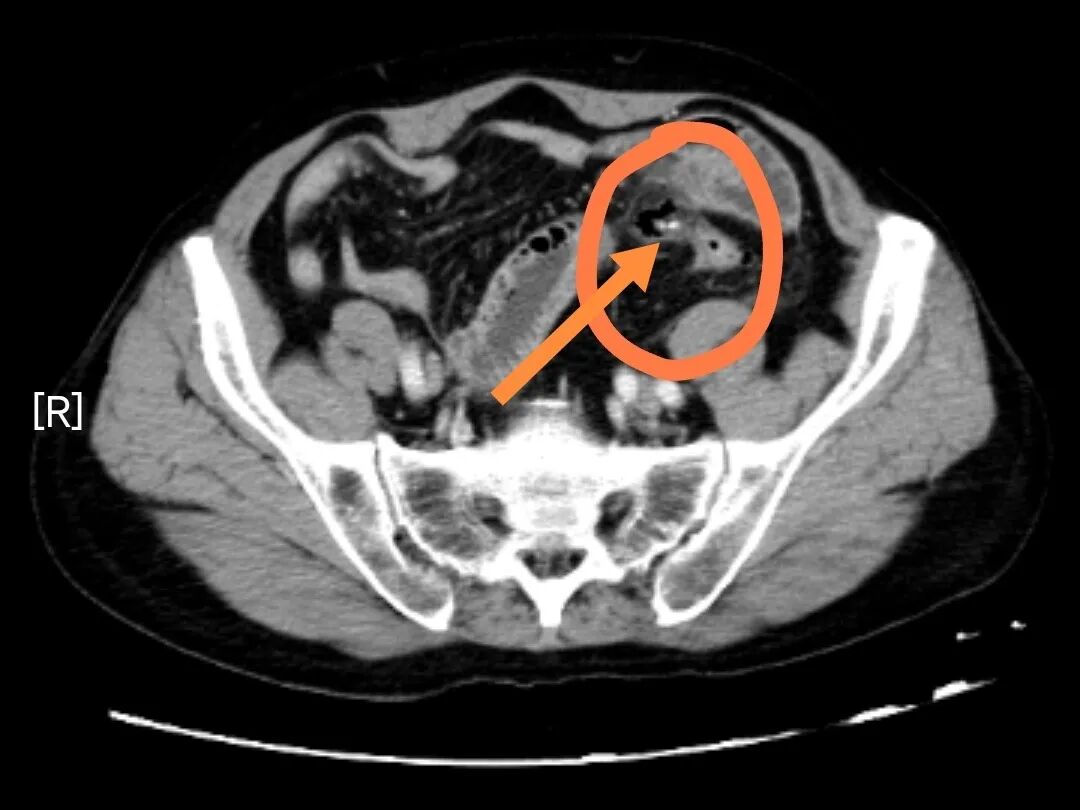

CT室内,机器运转的嗡鸣声在寂静中格外清晰。当影像出现在屏幕上时,在场所有医生都倒吸一口凉气——刘老伯的乙状结肠区域,一道长达42毫米的条状阴影赫然在目,像一把出鞘的利剑刺穿肠壁。周围弥漫的渗出灶和气体影,预示着肠穿孔已经发生,邻近小肠已出现粘连与扩张,腹腔感染正在蔓延。

影像诊断明确:乙状结肠异物伴穿孔、周围渗出;部分小肠扩张,考虑粘连性肠梗阻!